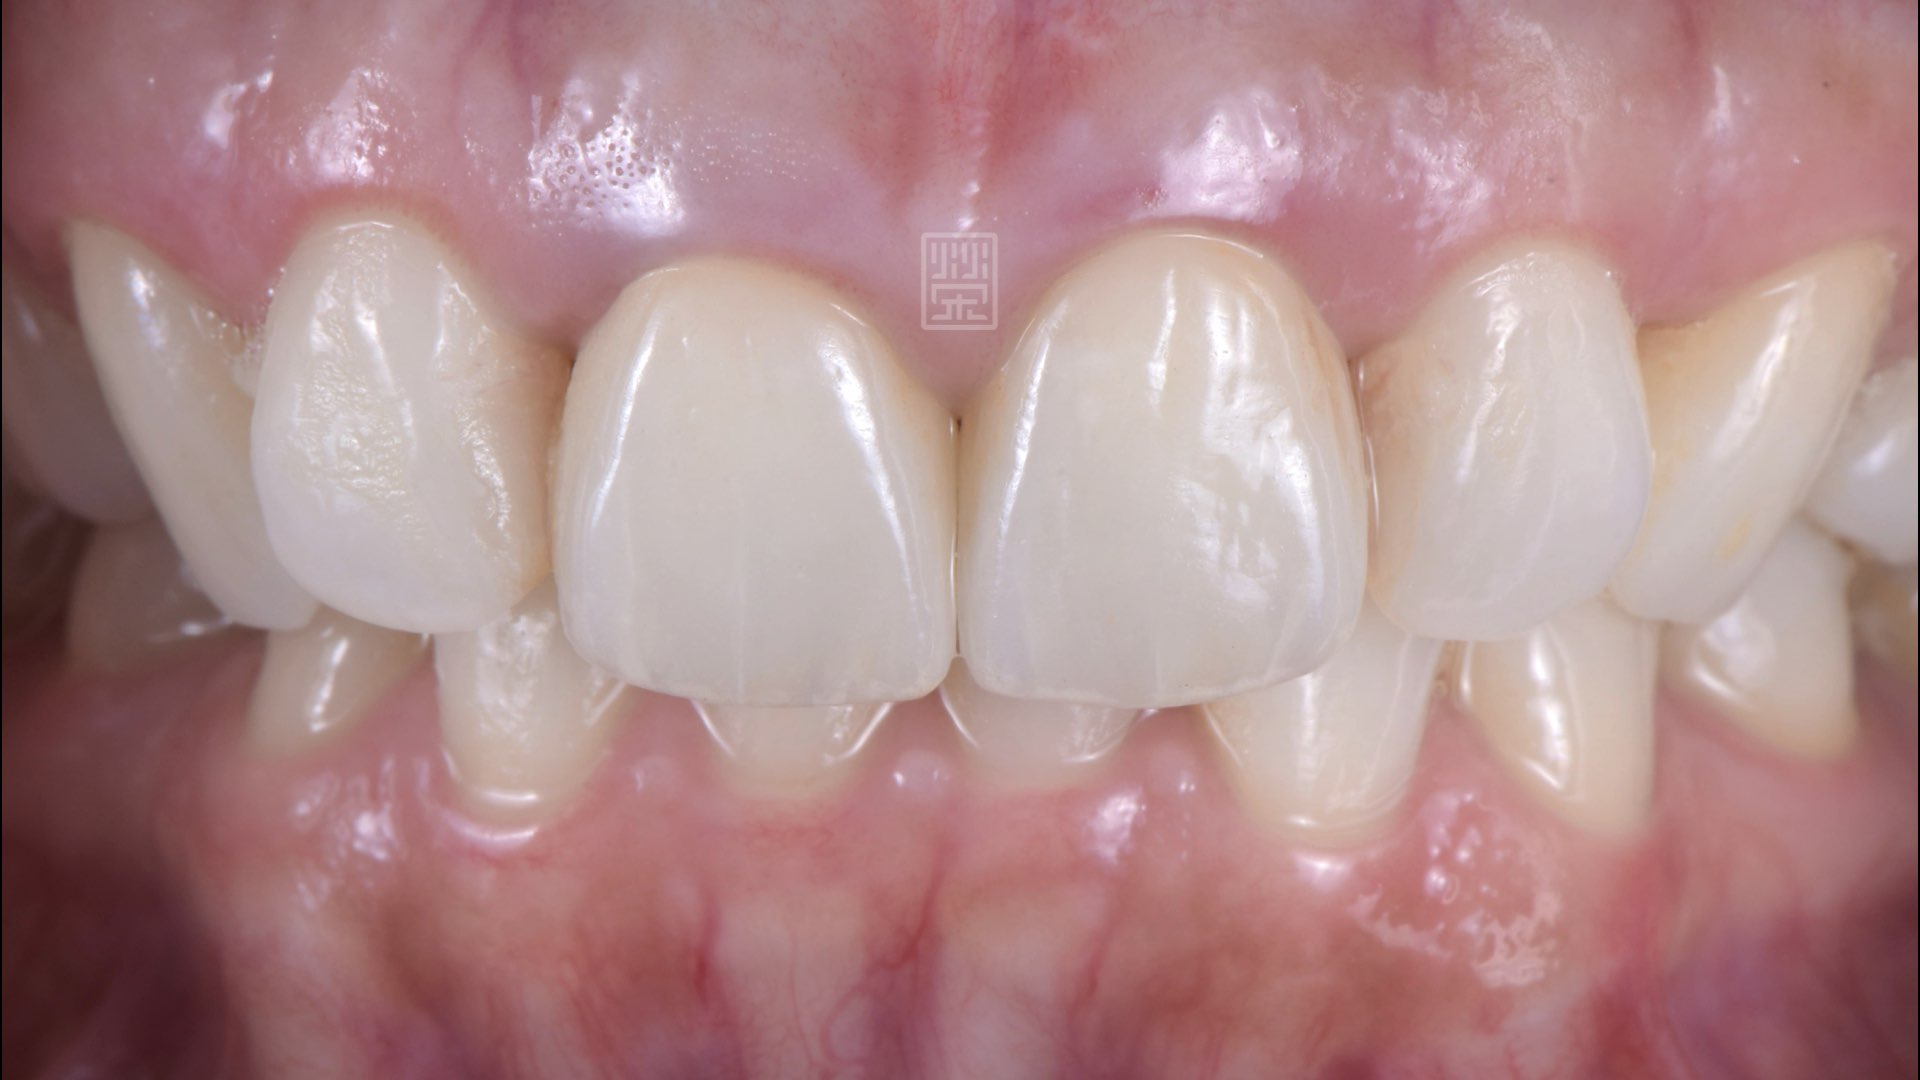

全瓷冠完成